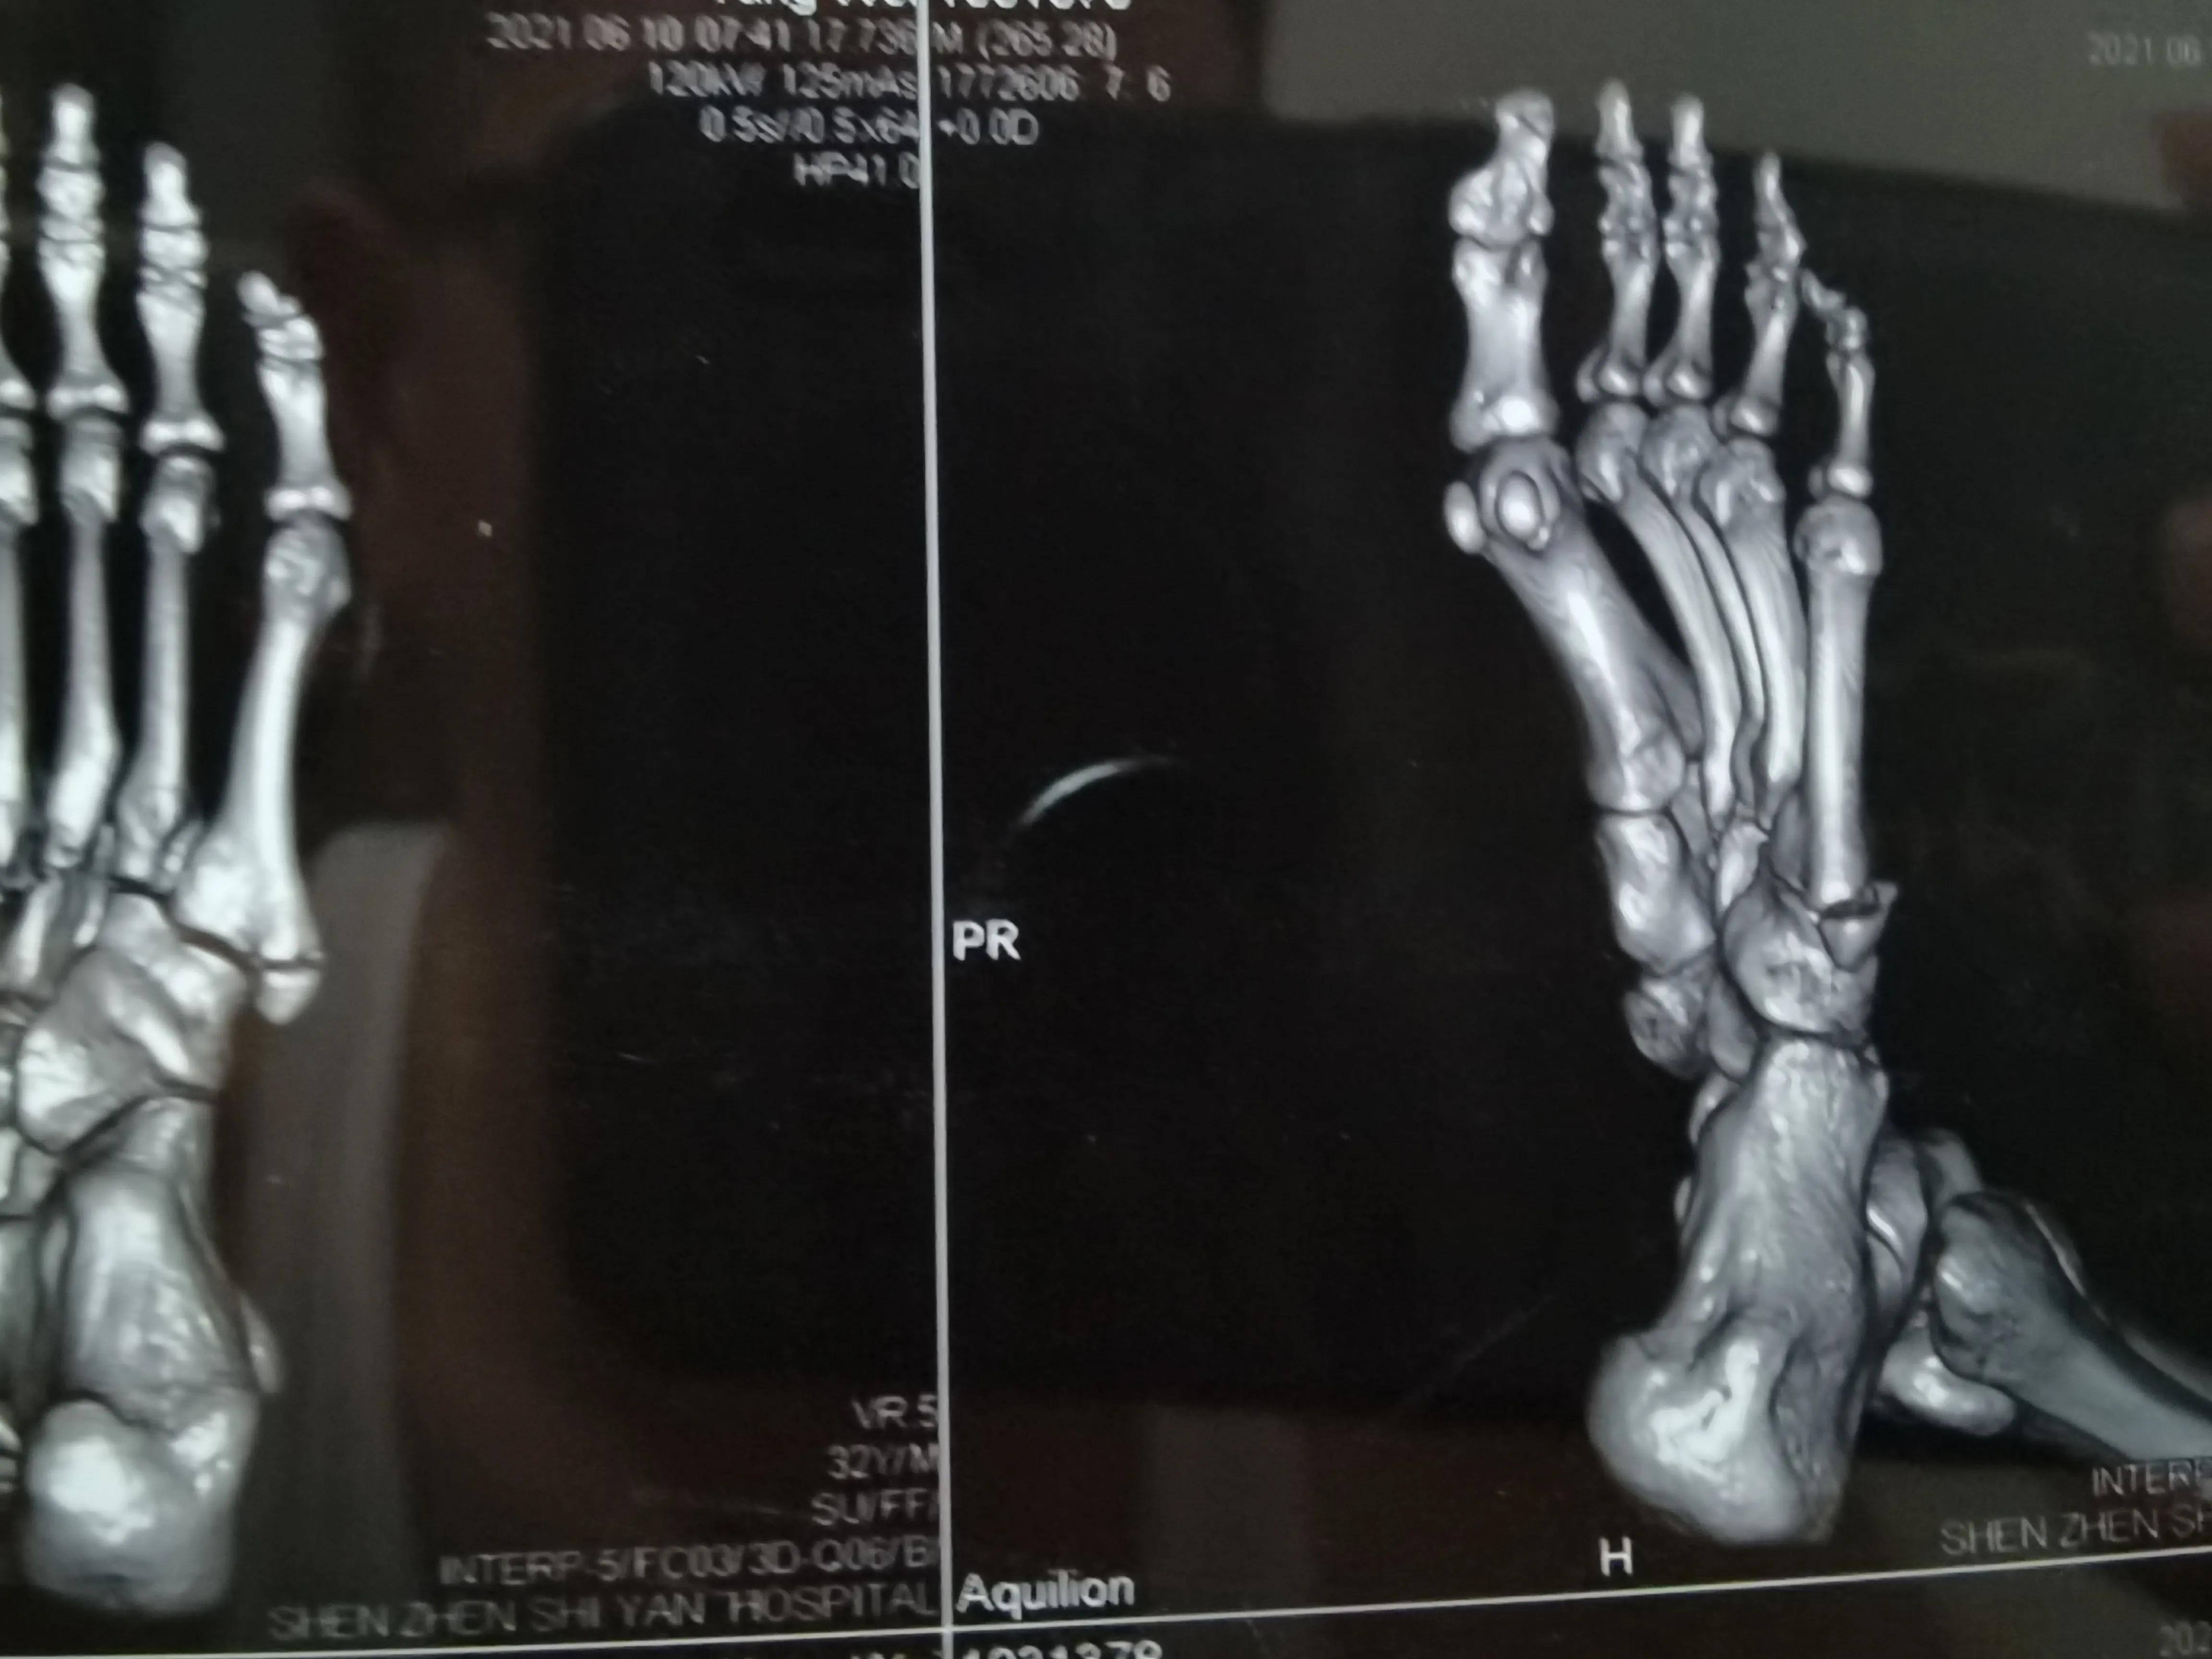

这是CT诊断书

看片子骨缝比较大了,有点移位,而且中间崩碎了一块,一直找不到,后来复查才发现那个碎片掉落在骨缝当中了

此图可以看见中间碎片在骨缝里面